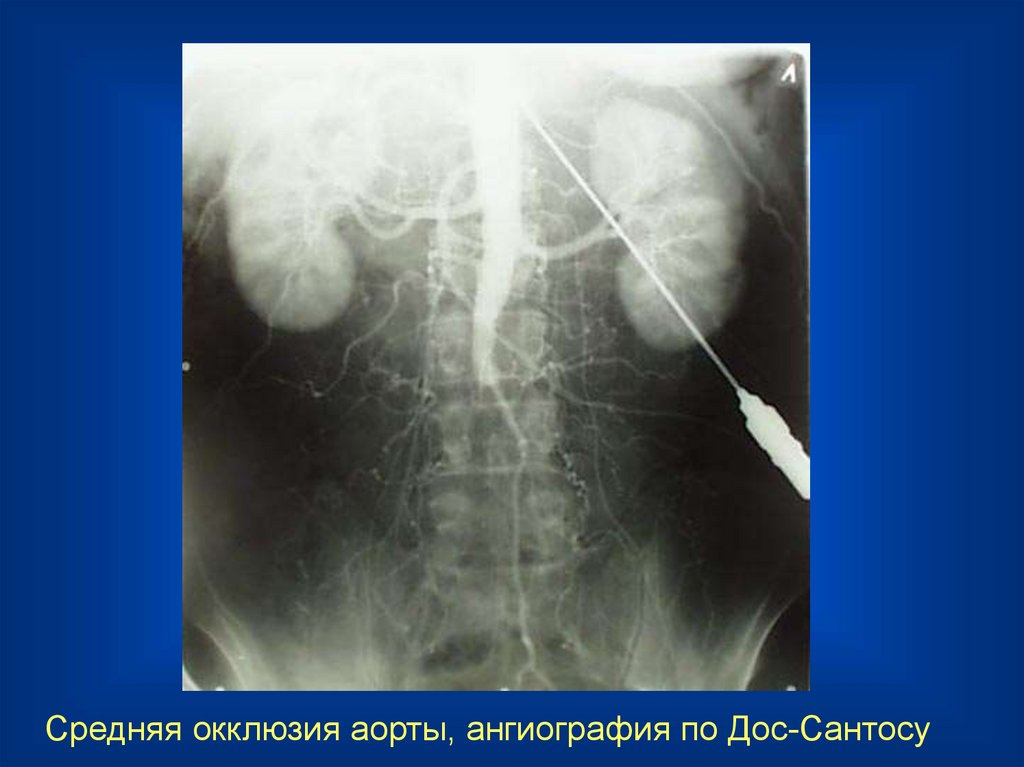

Средняя окклюзия аорты, ангиография по Дос-Сантосу